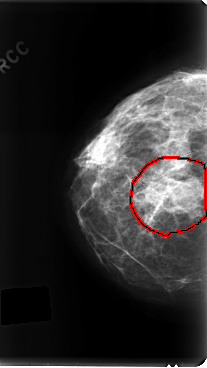

C_0197_1.RIGHT_CC

RIGHT_CC LINES 4776 PIXELS_PER_LINE 2688 BITS_PER_PIXEL 12 RESOLUTION 50 OVERLAY

FILE: C_0197_1.RIGHT_CC.OVERLAY

TOTAL_ABNORMALITIES 1

ABNORMALITY 1

LESION_TYPE MASS SHAPE IRREGULAR MARGINS ILL_DEFINED

ASSESSMENT 4

SUBTLETY 5

PATHOLOGY MALIGNANT

TOTAL_OUTLINES 1

BOUNDARY